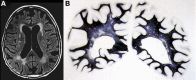

Vascular cognitive impairment (VCI) [vascular cognitive disorder (VCD), vascular dementia] describes a continuum of cognitive disorders ranging from mild cognitive impairment (MCI) to dementia, in which vascular brain injury involving regions important for memory, cognition and behavior plays an important role. Clinical diagnostic criteria show moderate sensitivity (ca 50%) and variable specificity (range 64-98%). In Western clinical series, VaD is suggested in 8-10% of cognitively impaired elderly subjects. Its prevalence in autopsy series varies from 0.03 to 58%, with means of 8 to 15% (in Japan 22-35%). Major types of sporadic VaD are multi-infarct encephalopathy, small vessel and strategic infarct type dementias, subcortical arteriosclerotic leukoencephalopathy (SAE) (Binswanger), multilacunar state, mixed cortico-subcortical type, granular cortical atrophy (rare), postischemic encephalopathy, and a mixture of cerebrovascular lesions (CVLs). They result from systemic, cardiac and local large or small vessel disease (SVD); their pathogenesis is multifactorial. Hereditary forms of VaD caused by gene mutations are rare. Cognitive decline is commonly associated with widespread small ischemic vascular lesions involving subcortical brain areas (basal ganglia and hemispheral white matter). The lesions affect neuronal networks involved in cognition, memory, and behavior (thalamo-cortical, striato-subfrontal, cortico-subcortical, limbic systems). CVLs often coexist with Alzheimer-type lesions and other pathologies; 25-80% of elderly demented show mixed pathologies. The lesion pattern of "pure" VaD differs from that in mixed dementia (AD + CVLs) suggesting different pathogenesis of both phenotypes. Minor CVLs, except for severe amyloid angiopathy, appear not essential for cognitive impairment in full-blown AD, while both mild AD-type pathology and SVD may interact synergistically in promoting dementia. However, in a large percentage of non-demented elderly individuals, both AD-related and vascular brain pathologies have been reported. Despite recent suggestions for staging and grading CVLs in specific brain areas, due to the high variability of CVLs associated with cognitive impairment, no validated neuropathological criteria are currently available for VaD and mixed dementia. Further clinico-pathological studies and harmonization of neuropathological procedures are needed to validate the diagnostic criteria for VaD and mixed dementia in order to clarify the impact of CVLs and other coexistent pathologies on cognitive impairment as a basis for further successful therapeutic options.